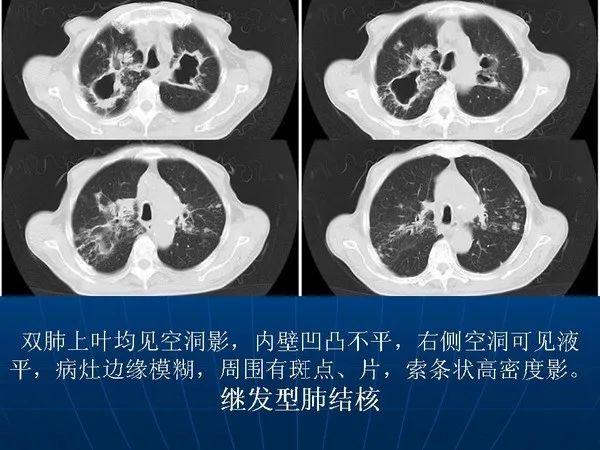

各型肺结核的典型影像表现

肺结核ct影像表现特点

肺结核ct片子图片特点